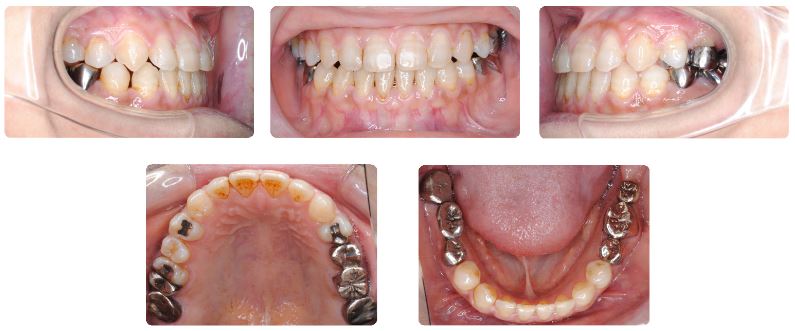

治療期間:1年2ヶ月

治療期間は1年2か月でした。

下あご歯列のみで固定式装置で治療をすすめていましたが、前歯が乗り越える際に上下顎前歯の切端が強くぶつかって痛いとのことでしたので、上あごにも固定式装置を装着しました。

咬合力が非常に強いため、前歯が乗り越える前後の治療期間には夜間のみ上あごにマウスピースを使用していただきました。